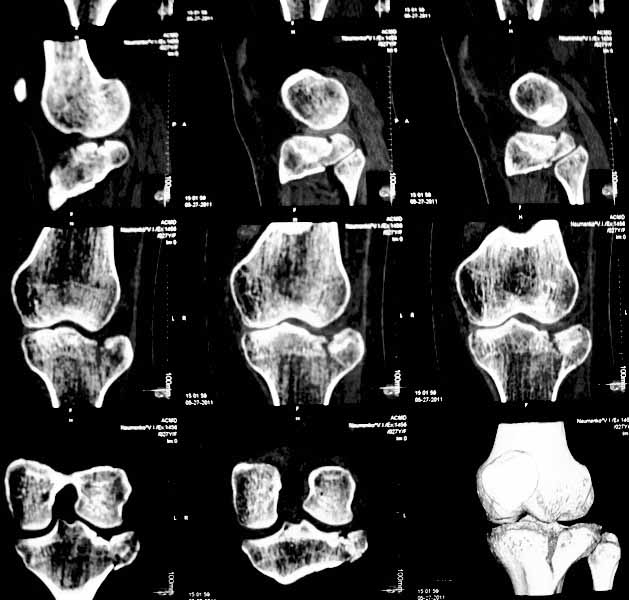

Застарелый перелом наружного мыщелка б.берцовой кости

Уважаемые коллеги. Хочу представить вам клинический случай и получить информацию в отношении тактики лечения данной пациентки. Возраст 27 лет, парапланеристка, получила травму в Индии 28 апреля 2011г, упала с мотоцикла, получила боковой удар по левому коленному суставу.

Первая помощь оказана в индийской клинике, установлен диагноз - Ссадины левого локтевого сустава, левого плеча, левой и правой стоп, повреждение связок левого коленного сустава (не указано каких). Со слов пациентки выполнены рентгеновские снимки голени (их не отдали). Наложена циркулярная рассеченная скотч-каст повязка без захвата стопы на левую ногу, рекомендовано консервативное лечение со сроком иммобилизации 6 недель. Пострадавшая оставалась в Индии и вернулась 17 мая.

26 мая обратилась ко мне за консультацией с вопросом – можно ли снять иммобилизацию немного раньше и начать ходить без костылей?. СКТ – снимки прилагаю.

-клинически – вальгизация коленного сустава, умеренная сглаженность контуров сустава, постиммобилизационная контрактура сустава, медиальной и латеральной нестабильности сустава нет.